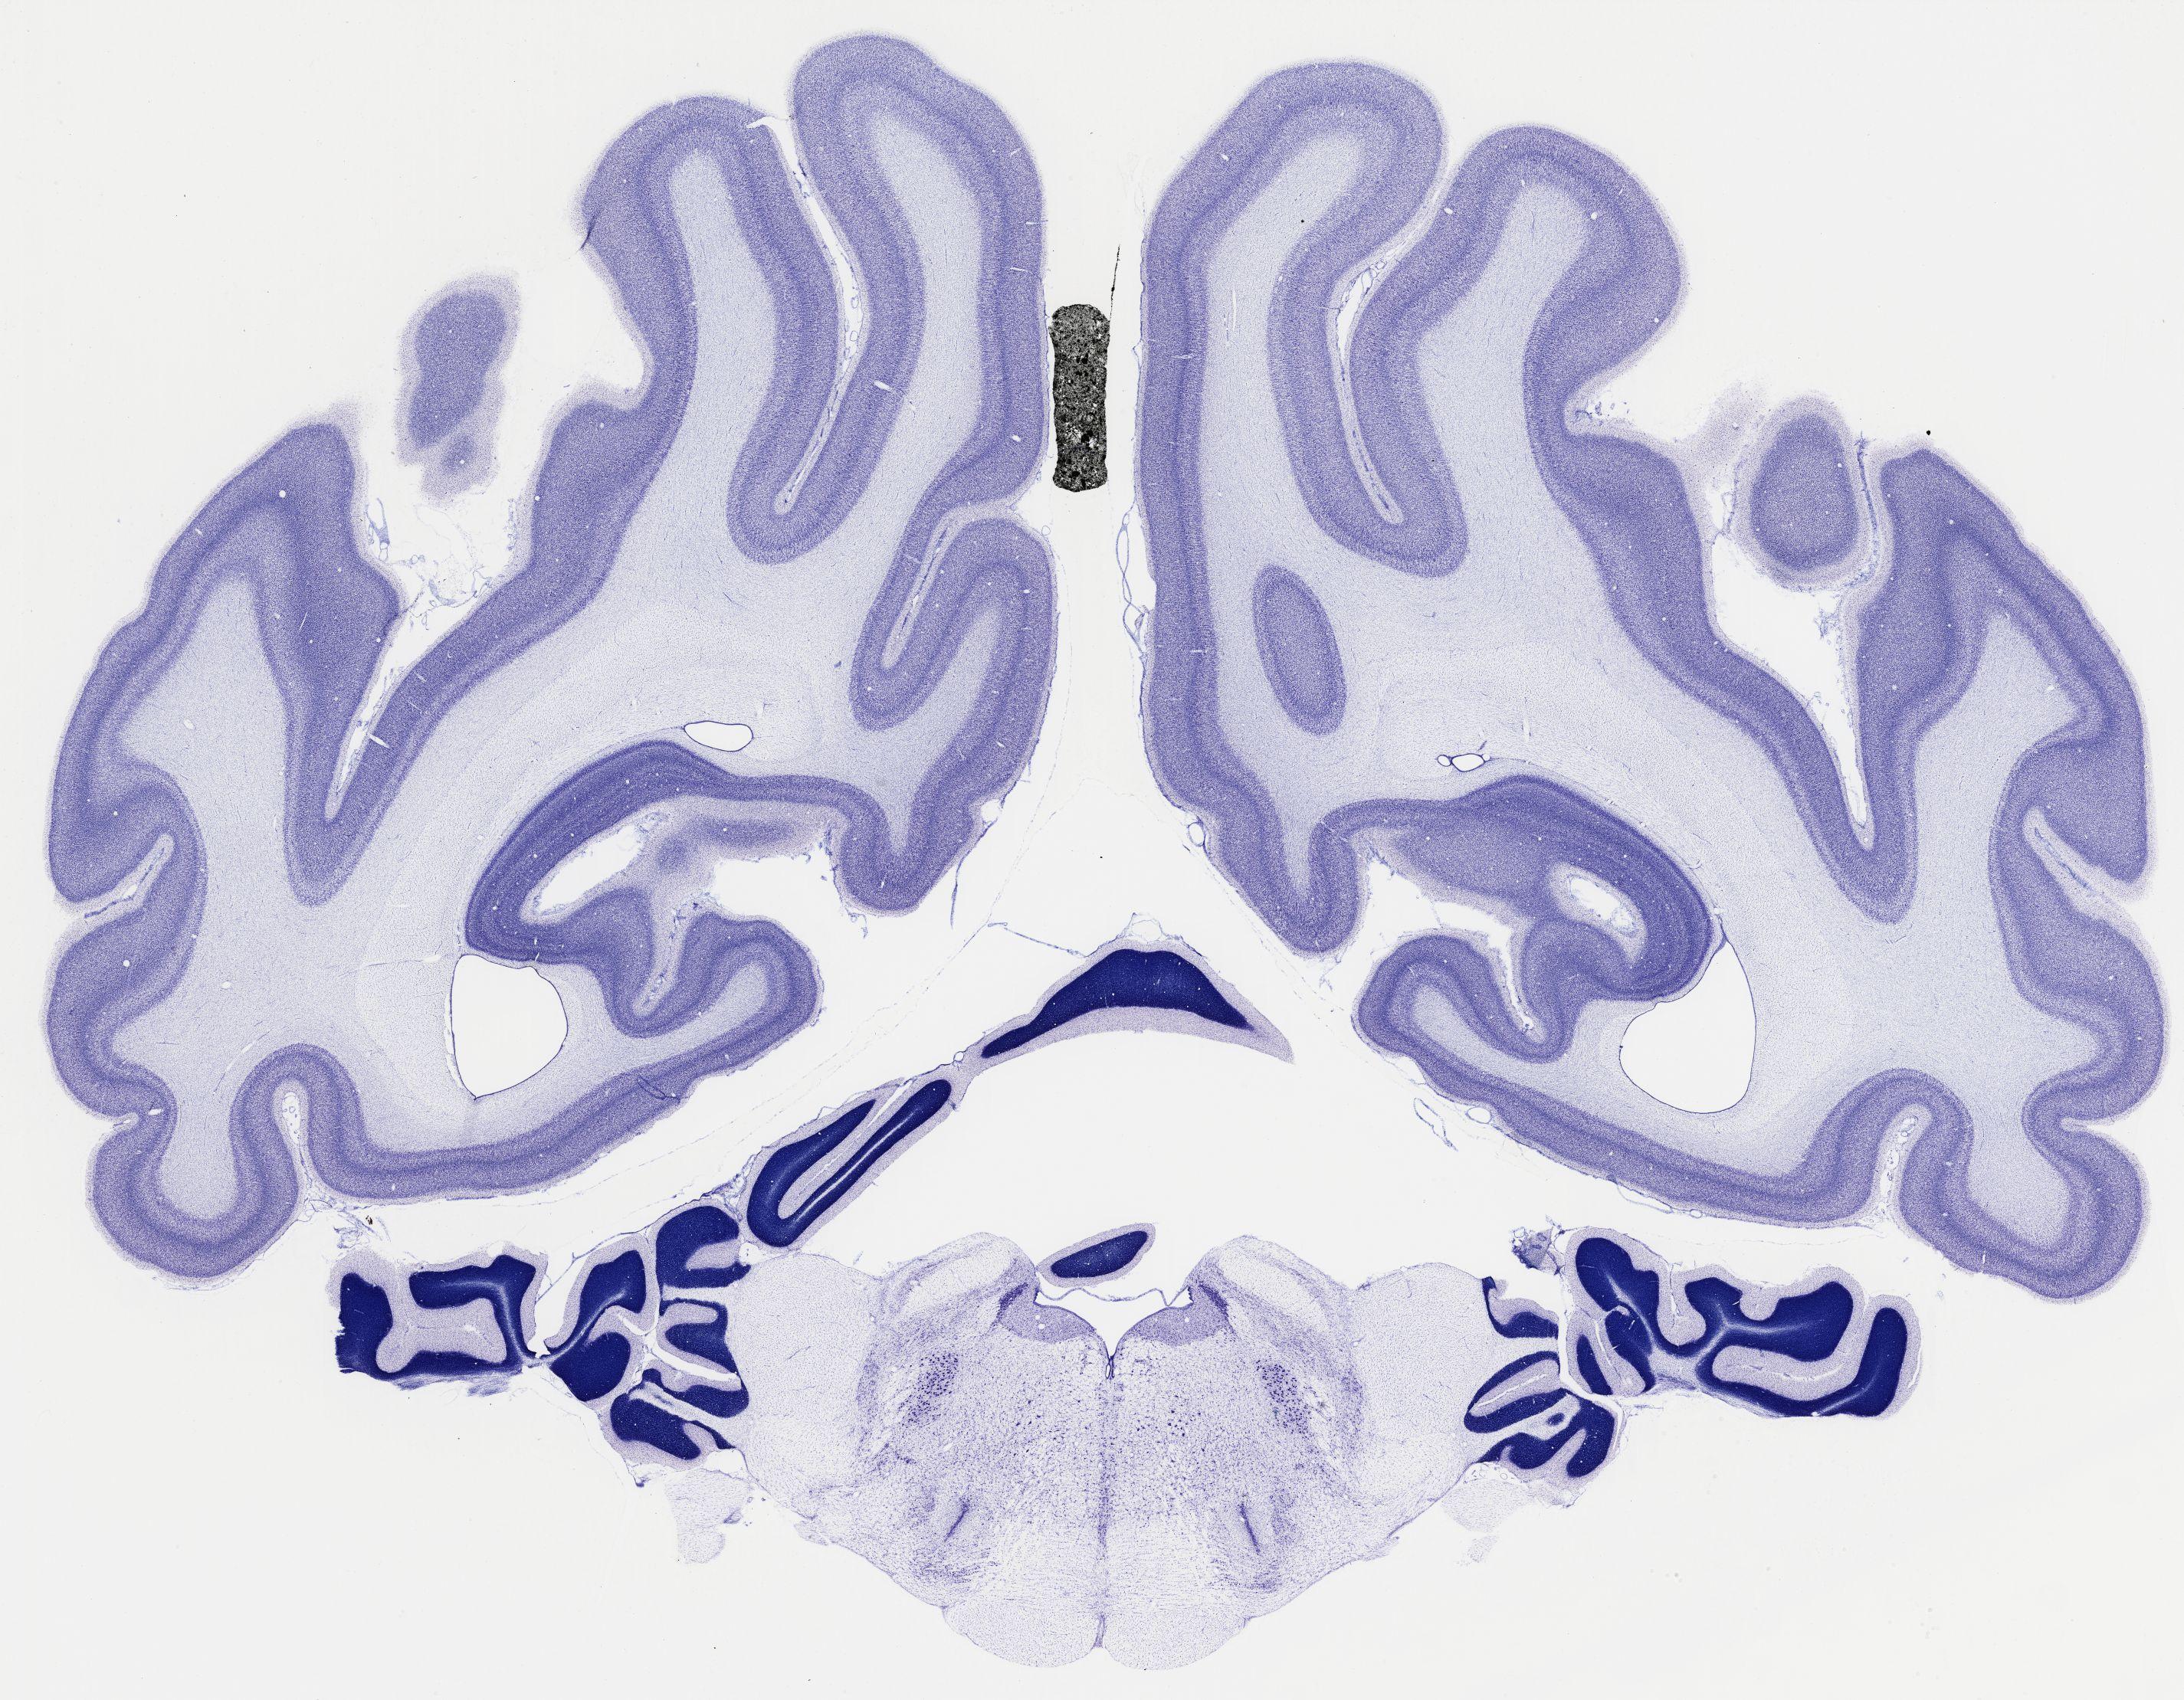

Datasets -> Chlorocebus Aethiops -> Nissl, coronal, histo, Whole-Brain, adult

[ Metadata ]   ·   Source: NeuroScience Associates

thumbnail

522